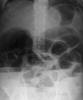

E de Paget

Osteoporosis circunscrita en Enfermedad de Paget.